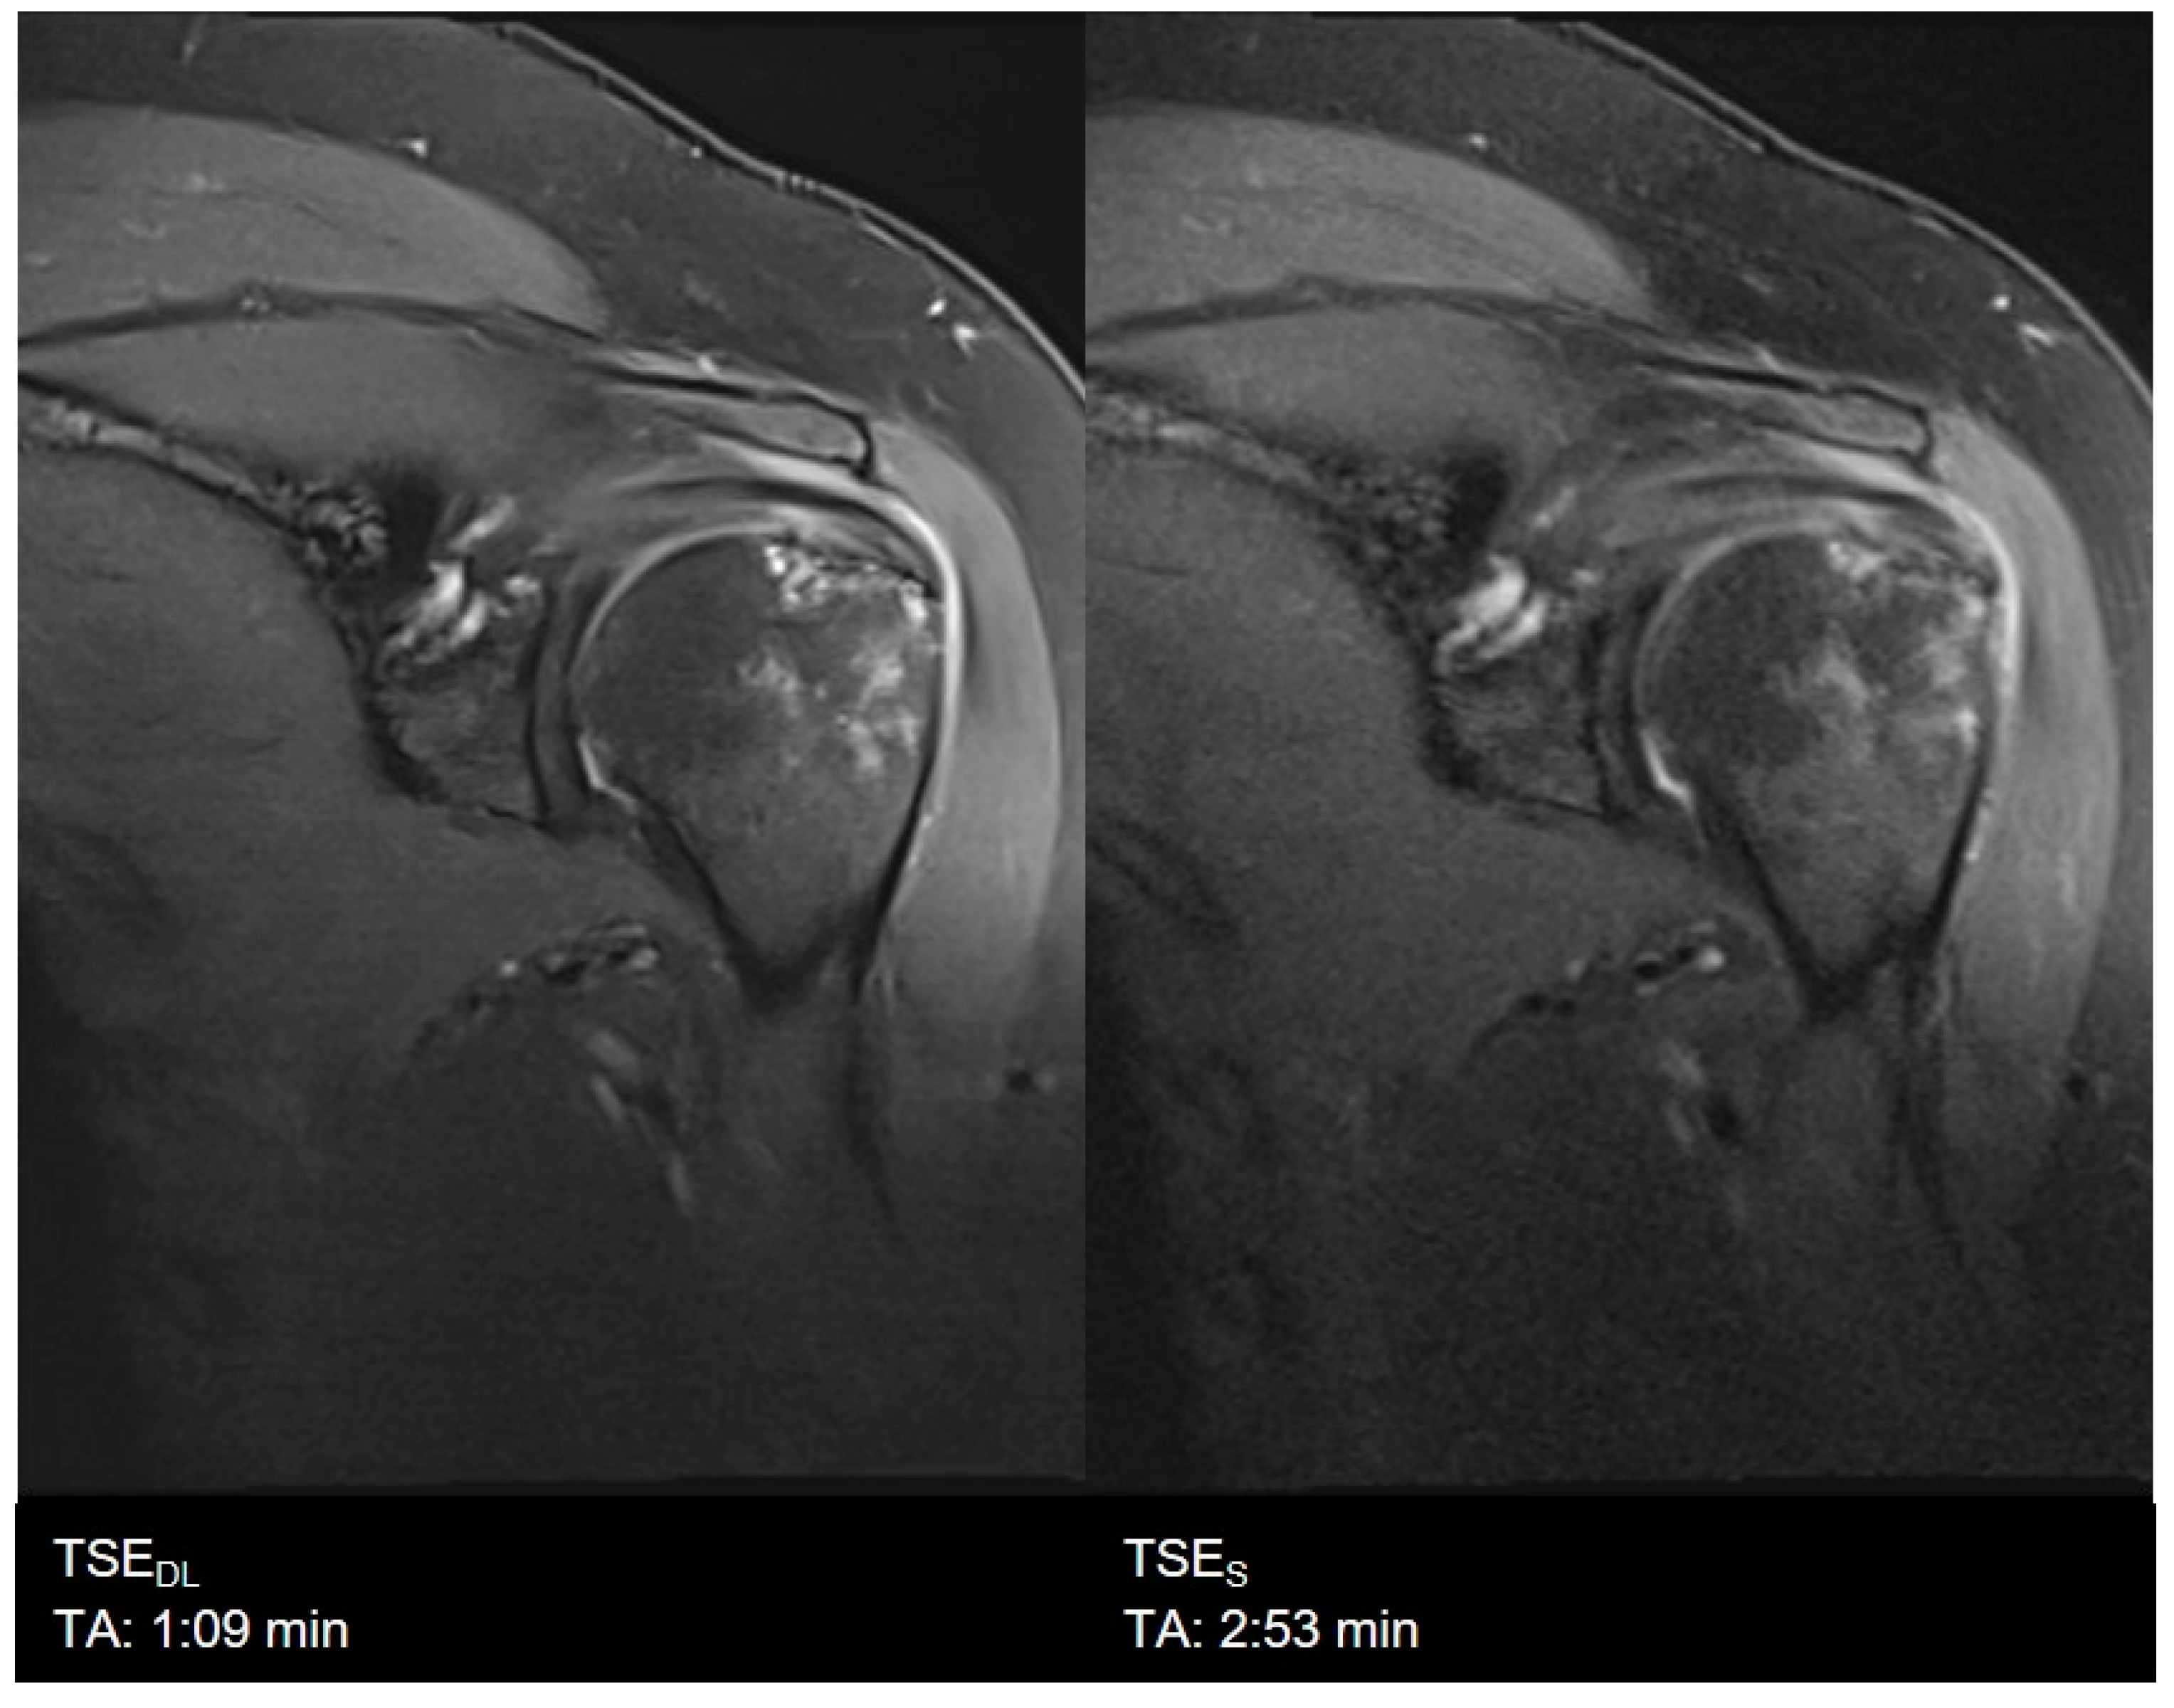

| Shoulder | TSES | TSE PD FS | axial | 2:14 | 180 | 0.6 × 0.6 × 3.0 | 1 | 2 | 2 | 3000 | 44 | 150 | 180 | 10.9 |

| coronal | 2:53 | 180 | 0.6 × 0.6 × 3.0 | 2 | 1 | 2 | 3300 | 42 | 150 | 191 | 10.6 | |||

| TSEDL | TSE PD FS | axial | 1:10 | 180 | 0.6 × 0.6 × 3.0 | 1 | 1 | 3 | 3520 | 44 | 150 | 180 | 10.9 | |

| coronal | 1:09 | 180 | 0.6 × 0.6 × 3.0 | 1 | 1 | 3 | 3000 | 42 | 150 | 191 | 10.6 | |||